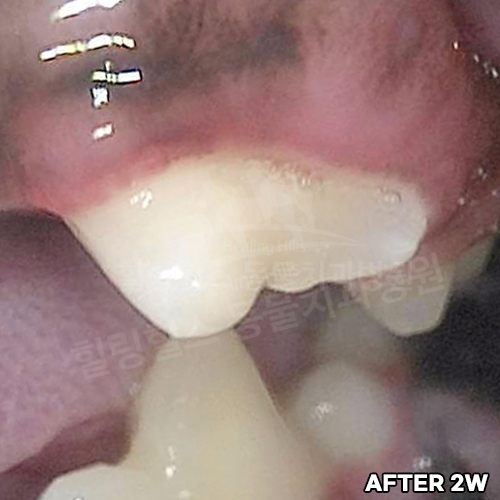

치아뿌리까지 파절된 강아지어금니 빨갛게 부어오른 잇몸치료~ 2년 뒤에 재생된 잇몸뼈 CT로 확인! 모든 동물병원에서 발치하자고 했지만 힐링힐스동물치과병원에서 되살려진 어금니!